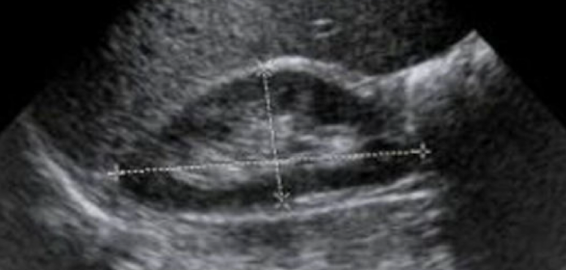

Which type of kidney image is this?

longtudinal